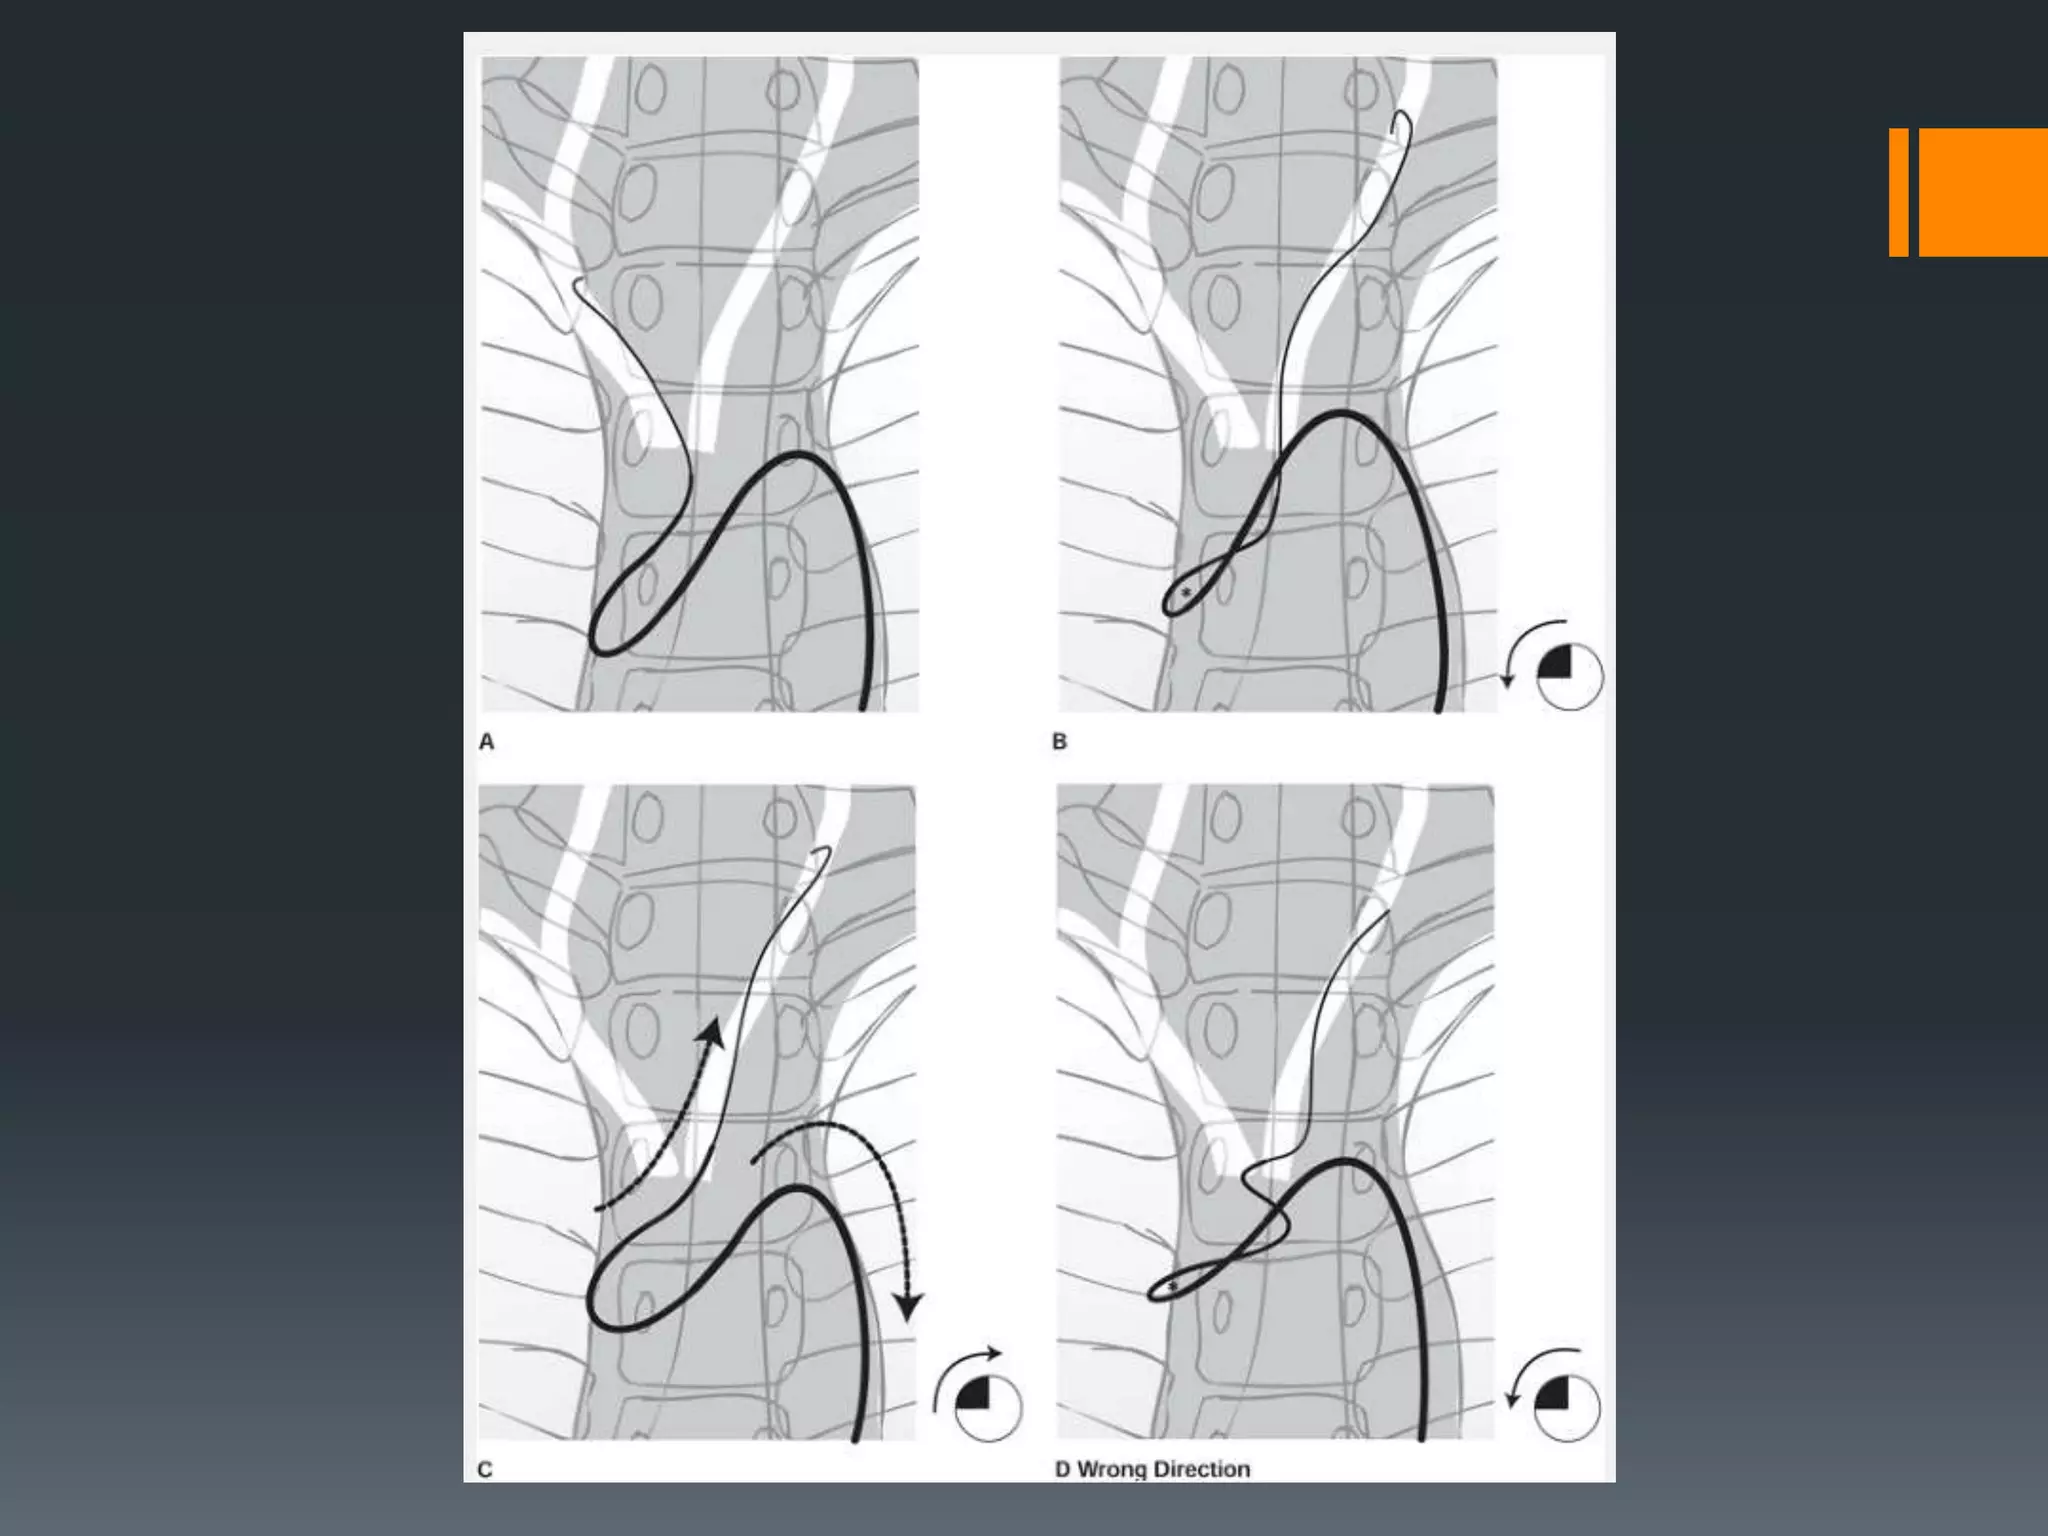

This document discusses tricks and techniques for difficult cannulations during neurointerventional procedures. It outlines strategies for accessing the aortic arch, internal carotid artery (ICA), and areas distal to aneurysms. Long sheaths, distal access catheters, and co-axial techniques are presented as options that have improved cannulation success. Guidance on sheath and catheter selection is provided for different vessel paths. The importance of catheter placement as high as possible in the ICA is emphasized. Reverse curve cannulations are also mentioned. Overall, the document stresses that careful cannulation is critical for procedural success and different strategies may be needed depending on the vessel target.